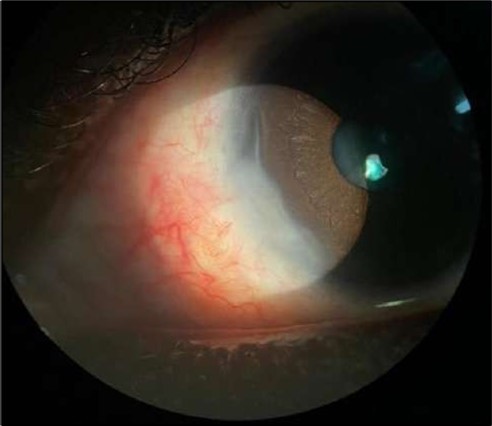

On the current presentation, Snellen VA was 6/6 in the right eye and 6/9 in the left eye, with normal IOP. The left eye demonstrated mild upper lid edema and intense nasal ciliary injection. Slit-lamp evaluation revealed a crescentic area of stromal corneal melting between 7 and 10 o’clock nasally, with overhanging edges and a fluorescein-positive base. No corneal infiltrates were present, and the surrounding stroma remained clear. The anterior chamber was deep and quiet, lens was transparent, pupil was round and reactive & normal posterior segment. Anterior segment optical coherence tomography (AS-OCT) confirmed a localized ulcer, measuring 1324 µm in horizontal width and extending to a depth of 380 μm, compared with an adjacent healthy corneal thickness of 824 µm, corresponding to approximately 46.1% stromal thinning (Figure 1a, Figure 1b, Figure 1c)

Figure 1a.Left eye (OS), on presentation. Slit-lamp image: crescent-shaped peripheral corneal ulceration located nasally, with severe adjacent conjunctival injection, peripheral thinning, and stromal infiltration.

Two weeks post-surgery, the left eye showed significant healing, with a small conjunctival granuloma and vascularization at the ulcer margins. The cornea was clear with a central leading edge nasally, deep and quiet anterior chamber and clear lens. VA 6/6 bilaterally and IOP normal. Histopathology of excised conjunctiva showed non-keratinized squamous epithelium with superficial erosions, stromal elastosis, hemorrhage, and inflammatory infiltration, but no signs of granulomatous disease, malignancy, or viral evidence, findings consistent with idiopathic localized inflammatory process. The patient reported significant relief and satisfaction post-surgery, resuming normal activities. Treatment continued with oral prednisolone 25 milligrams every other day, tobramycin-dexamethasone ointment twice daily, and preservative-free artificial tears four times daily Figure 4, Figure 5a, Figure 5b, Figure 5c, Figure 5d.

Figure 4.OS. Slit-lamp photograph showing a partially quiet ocular surface two weeks following surgical excision of adjacent perilimbal conjunctiva.